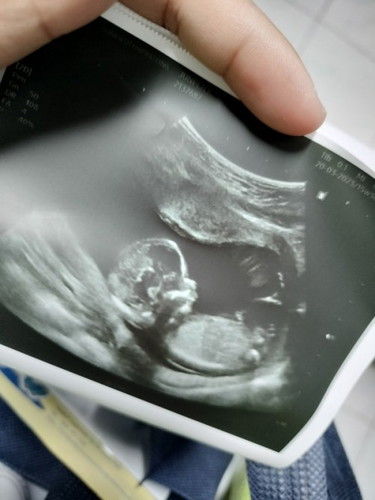

พอจะเห็นเพศน้องไหมคะว่าเพศอะไร คุณหมอบอกเพศชาย แต่คุณแม่ไม่แน่ใจ คะ

ที่เห็นชัดแจ๋ววคือ จมูกน้องงโด่งมากลูกก🤣😂😂👶👶👶

บ้านนี้ยังไม่เห็นเพศ แต่เห็นจมูกพุ่งเหมือนกันค่ะ ตอนคลอดอย่าลืมเอาออกมาด้วยนะลูก😂😂

ตัวใหญ่.จมูกโด่ง.